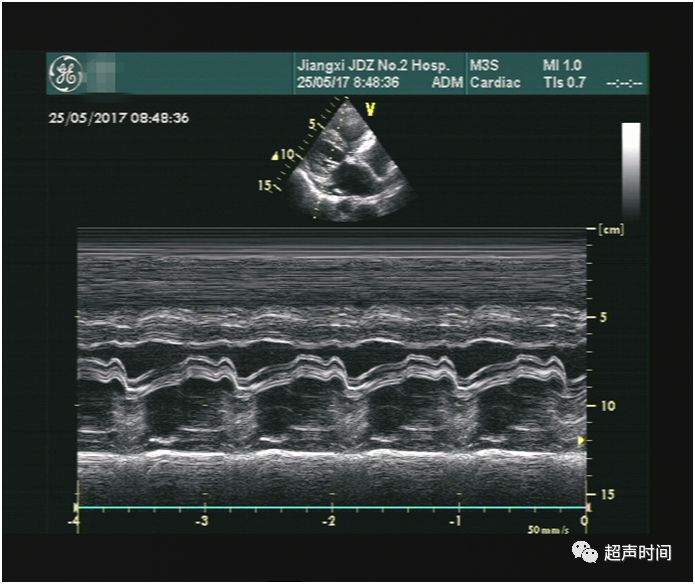

超声所见:M 型超声显示二尖瓣呈平台样改变,前后叶同向运动,回声增厚增强,开放受限,开放幅度约 0.94 cm,描迹瓣口面积约 1.8 cm²(图 1 和 2)。频谱多普勒示二尖瓣前向血流增快,PHT 估测瓣口面积约 1.8 cm²(图 3)。CDFI 示收缩期三尖瓣可见轻中度反流,据此估测的肺动脉收缩压正常(图 4)。房间隔中部见约 1.2 cm 连续中断,可见连续性左向右分流血流信号,峰速115 cm/s (图 5~图 7)。

图 1 M 型超声示二尖瓣的平台样改变